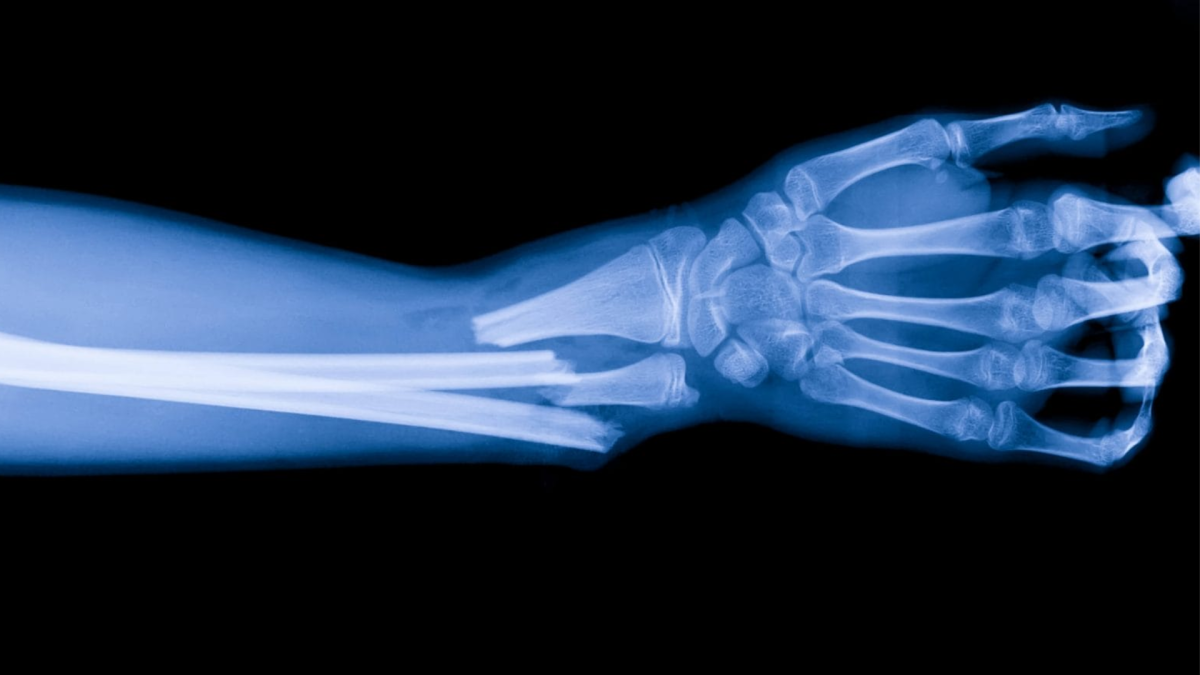

O fractură reprezintă întreruperea continuităţii osului, care poate apărea din cauza unui traumatisme directe sau indirecte. Din momentul în care osul este imobilizat (prin ghips, atelă, fixare chirurgicală etc.), corpul intră într-un proces de vindecare care implică mai multe faze: inflamaţie, formare de calus (fibro-cartilaginos, apoi osos), remodelare osoasă. Membrul imobilizat suferă adesea de atrofie musculară, rigiditate articulară, pierdere de mobilitate – iar recuperarea vine să corecteze toate aceste consecinţe. De aceea, dacă recuperarea nu este corect efectuată, funcţia membrului poate rămâne compromisă.

Fracturile pot apărea în urma unui accident, a unei căzături banale sau a unui efort mai mare decât poate suporta osul. În funcție de vârstă, stil de viață și activitate, anumite zone ale corpului sunt mai expuse.

Nu toate fracturile se vindecă la fel. Unele necesită doar câteva săptămâni de imobilizare şi exerciţii uşoare, în timp ce altele pot presupune luni de recuperare complexă, intervenţii chirurgicale şi reeducarea completă a mişcării.

Durata variază în funcţie de tipul şi gravitatea fracturii, de vârstă, de starea generală de sănătate şi de respectarea programului de recuperare. În general, perioada poate fi între 4 săptămâni şi 6 luni.